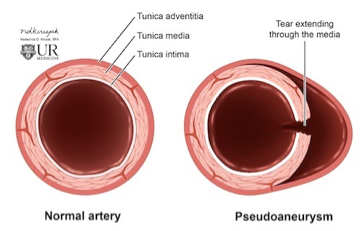

What aneurysm shape is the following

hematoma that forms as the result of a leaking hole in an artery

Pseudoaneurysm

What does this refer to

What does this refer to

Communication through a “stalk” from the artery to the “sack”

Hematoma often develops within the sack

Pseudoaneurysm